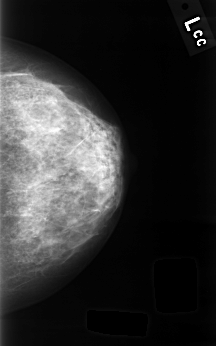

C_0334_1.LEFT_CC

LEFT_CC LINES 4496 PIXELS_PER_LINE 2800 BITS_PER_PIXEL 12 RESOLUTION 50 NON_OVERLAY